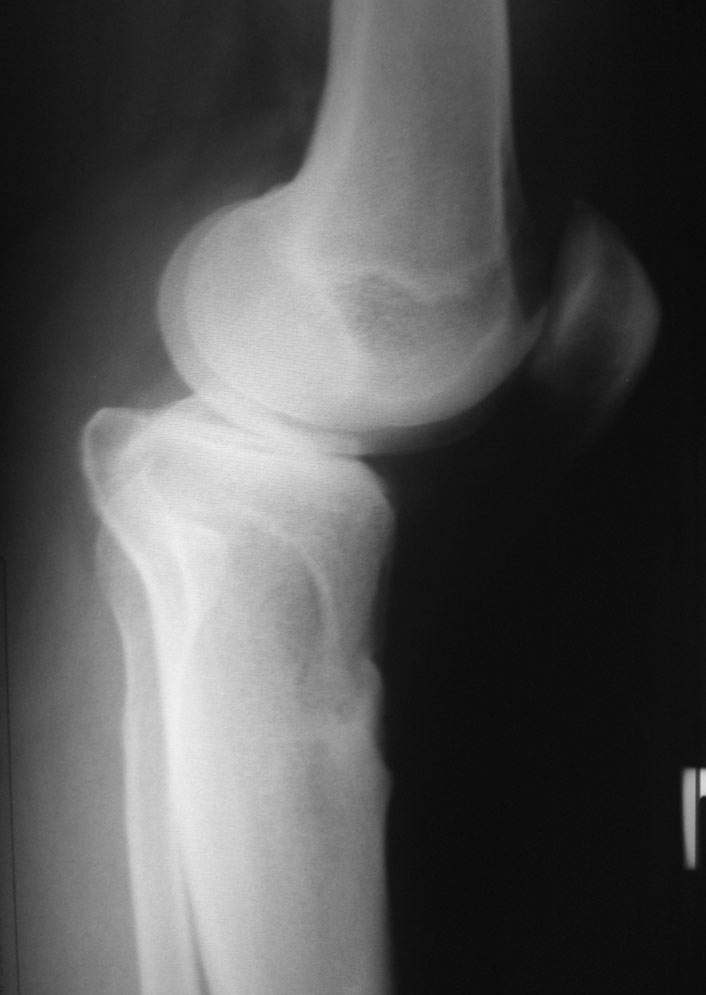

Уважаемый доктор Зайцев! Причина деформации проксимальной тибии у Вашего пациента - преждевременное и несимметричное закрытие зоны роста передней части проксимальной ростковой зоны б/б кости в следствии окультной травмы произошедшей в возрате 10-12 лет. Есть 2 причины рекурвационной деформации в области коленного сустава - мягкотканевая и костная.В данном случае Вы имеете дело не с рукурвацией коленного сустава, а с рекурвационной деформацией проксимальной голени. "Заднего выдвижного положения" на самом деле нет.То, что Вы видите на боковом снимке - это не задний подвывих голени - это снимок, сделанный в сгибании коленного сустава. Дело в том, что костные дефорсации в области коленного хорошо компенсируются за счёт движения в суставе. поэтому то, что вы видите, как задний подвывих на самом деле - сгибательное положение колена.

Это можно проверить очень просто - надо сделать стресс рентгенограмму в положении полного разгибания коленного сустава.Для этого посадите больного на стул, пятку поставьте на другой стул, дайте пациенту кассету 30Х40 держать с наружной стороны колена, и попросить ренгентехника сделать латеральный снимок с втутренней стороны. Сделав снимок здорового колена, Вы сможете расчитать деформацию.

10.-Рассмотрим представленную деформацию в боковой рентгенологической проекции.

Несложные расчеты на изготовленной скиаграмме (см. рис.1 ) показывают ,что суставная поверхность проксимального отдела б/б кости, находится в положении сгибания примерно 30 гр. Плоскость деформации лежит в сагитальной плоскости. Истинный угол деформации равен примерно 15 гр., с вершиной на 4-4.5 см. (примерно) дистальнее края суставной поверхности.

Вам представленна склаграмма боковой R – гр болного вынесенного на обсуждение.

А – ось бедра.

Б – линия Blumensaat/

В – имеющаяся линия суставной поверхности б/б кости.

Г – положение суставной поверхности в норме, по отношению к продольной оси б/б кости.

Д – продольная ось голени.

86 гр. (Г-Д) отношение суставной полверхности к оси голени.

~ 30 гр. – положение сгибания.